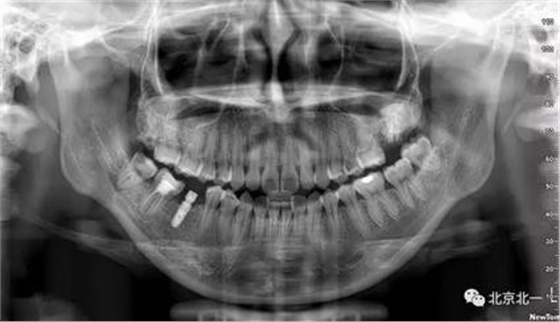

圖二:全景片見27區(qū)高密度影像,考慮智齒埋伏,拍CBCT確認(rèn)。